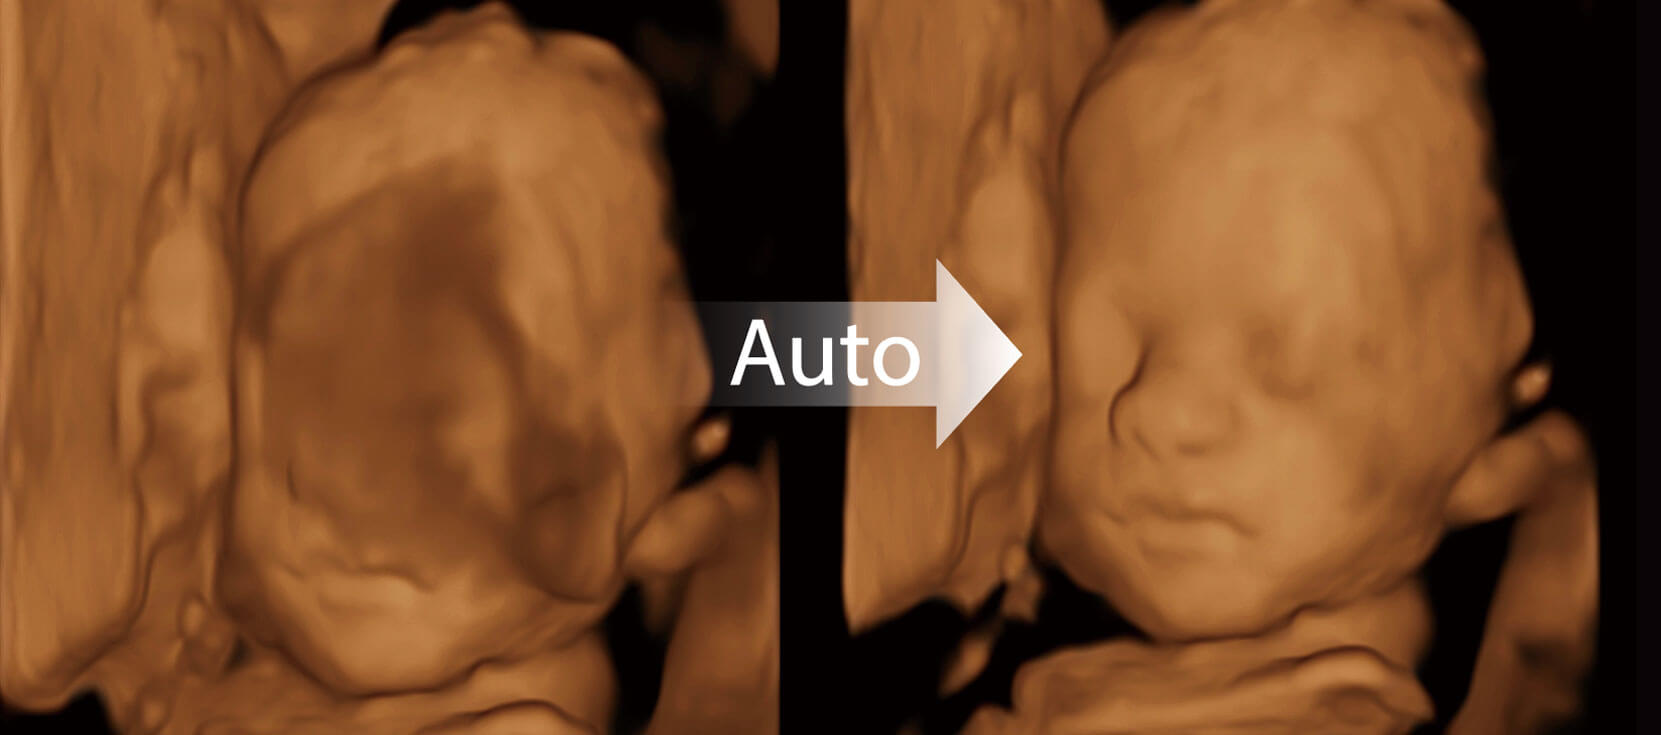

Auto Face

Tự động nhận diện khuôn mặt

Tự động tối ưu hóa khuôn mặt thai nhi 3D

Tự động loại bỏ tình trạng tắc nghẽn ở phía trước khuôn mặt thai nhi

Nhận dạng chính xác cấu trúc giải phẫu khuôn mặt thai nhi